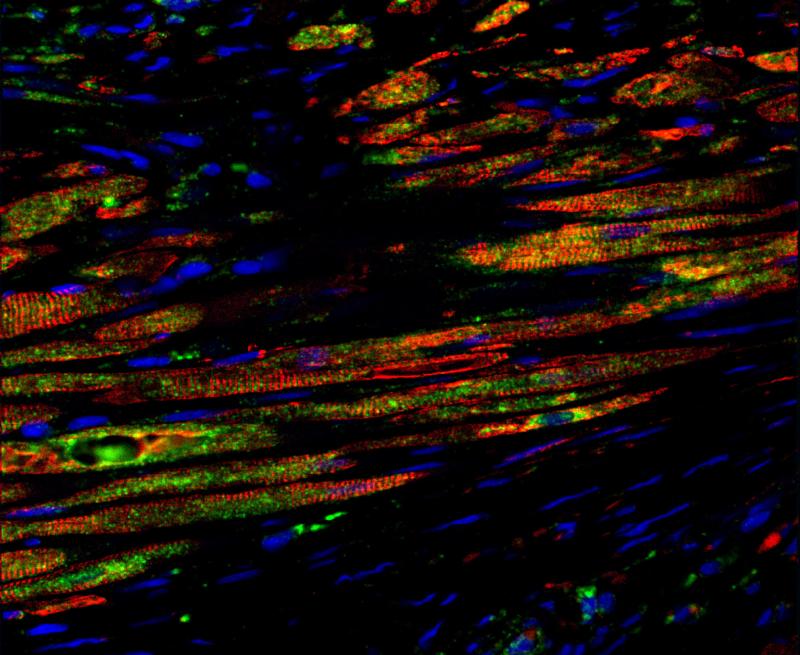

Bei diesem Bild zeigt Grün die von den transplantierten Stammzellen neugebildeten Myozyten. Rot stellt Myozyten dar, Blau die Zellkerne. Rot und Grün zusammen bedeutet, dass die transplantierten Stammzellen neue Myozyten gebildet haben. (Journal of the American College of Cardiology / Elsevier)

Bei diesem Bild zeigt Grün die von den transplantierten Stammzellen neugebildeten Myozyten. Rot stellt Myozyten dar, Blau die Zellkerne. Rot und Grün zusammen bedeutet, dass die transplantierten Stammzellen neue Myozyten gebildet haben. (Journal of the American College of Cardiology / Elsevier)

Bei diesem Bild zeigt Grün die von den transplantierten Stammzellen neugebildeten Myozyten. Rot stellt Myozyten dar, Blau die Zellkerne. Rot und Grün zusammen bedeutet, dass die transplantierten Stammzellen neue Myozyten gebildet haben. (Journal of the American College of Cardiology / Elsevier)